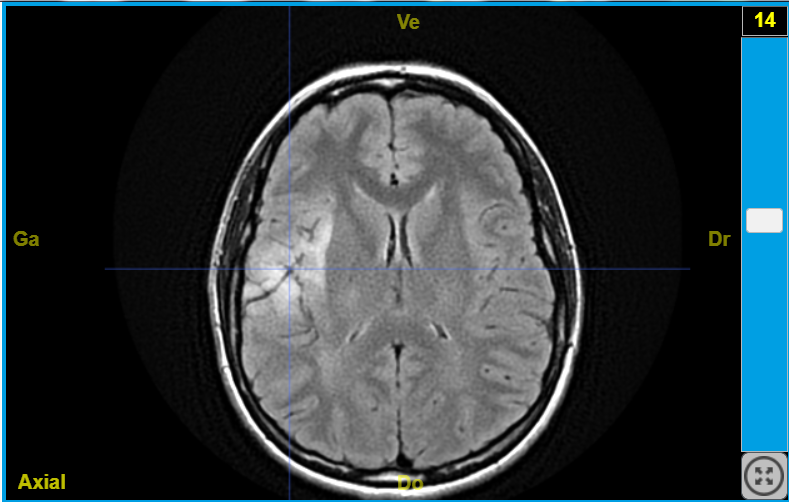

IRMsujet12222PathologieTumeurAudition T2Flair  LCR NOIR